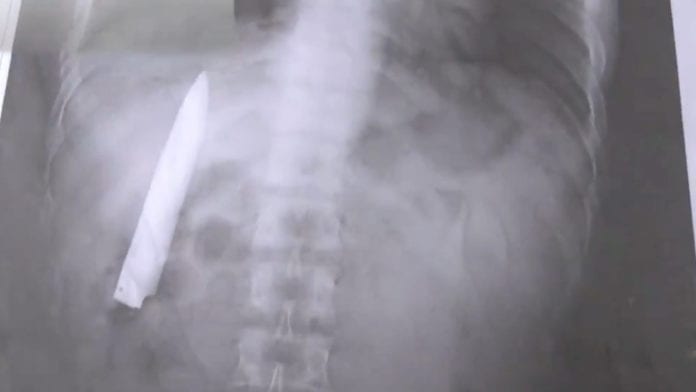

El sujeto, identificado como Kent Ryan Tomao, acudió en enero de 2020 para un hospital luego de que lo atacasen unos delincuentes, personal médico le suturó la herida de inmediato sin hacer una radiografía y dejaron la hojilla adentro.

El pasado 23 de marzo Ryan Tomao fue a un hospital para hacerse unas pruebas de rayos X, ya que estaba postulando a un trabajo. Aunque sentía un poco de dolor cuando hacía frío, no percibía más nada.